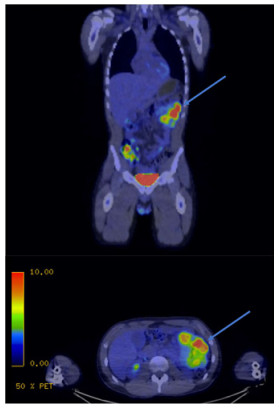

Jejunal Leiomyosarcoma in a Young Adult: Distinguishing from Gastrointestinal Stromal Tumor through Radiographic, Histologic, and Epidemiologic Analysis – A Case Report